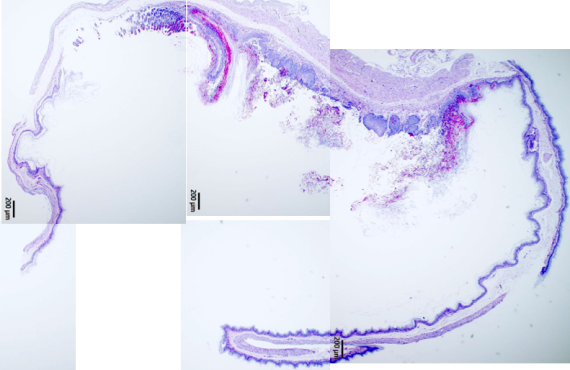

使用免疫缺陷小鼠建立特定感染病原動物模式,用此動物模式評估特定藥物或益生菌對不同感染性疾病的發生或症狀是否具抑制或改善功效。 實績: 1.抗真菌藥物臨床前測試:分析藥物或生物製劑抑制腸胃道念珠菌感染及對不同抗藥性念珠菌的影響 2.益生菌降低腸胃道病原感染測試:分析益生菌抑制腸胃道念珠菌或困難梭孢菌感染的效果